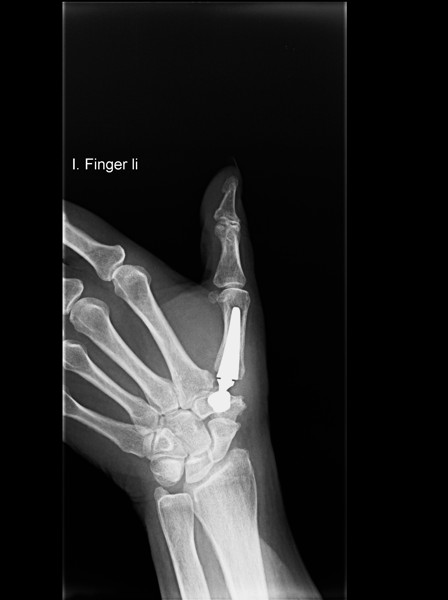

Eines dieser Verfahren ist der Einsatz einer Daumensattelgelenksprothese (Duokopfprothese). Sie hat anderen Eingriffen gegenüber wesentliche Vorteile, da Ihre Hand nach der Operation wieder schneller beweglich sein wird. Zudem verbessert sich Ihre Griffkraft und Sie werden schneller arbeitsfähig sein.

Weitere Verfahren sind die Entfernung des Vieleckbeins (Os trapezium) oder auch die Versteifung des Daumensattelgelenks (Arthrodese).

Rhizarthrose Behandlung mit einer Daumensattel-Gelenksprothese

Ihre Hand wieder voll im Einsatz: Künstliches Daumensattelgelenk bei Rhizarthrose